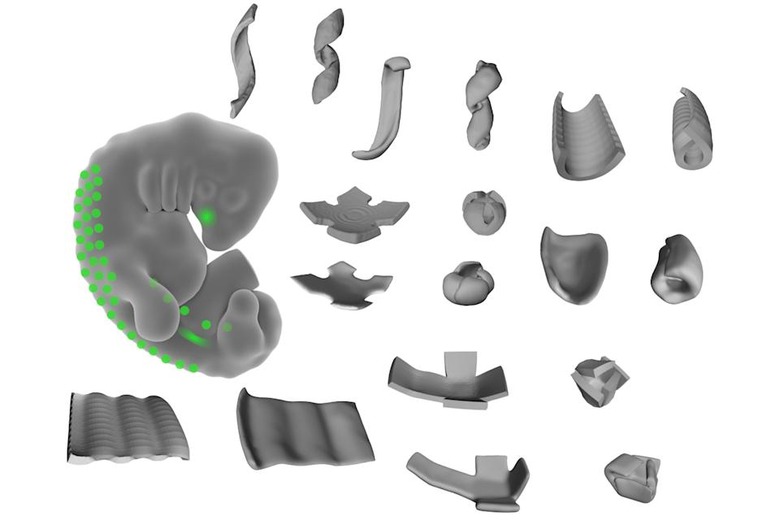

Never mind 3D-printing organs — the real dream is to make the tissue itself bend to your will, and UCSF scientists have managed just that. They've discovered that they can 'hack' special cells that help fold tissue (mesenchymal cells) to create 3D shapes out of live tissue. The trick is to lay out these cells in specific patterns that "tug" on other cells' extracellular matrix fibers. You can create surprisingly diverse items, ranging from simple bowls and ripples to decidedly unnatural items like cubes and coils.